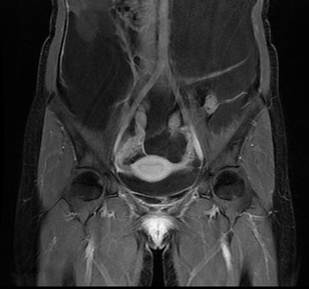

Se realizó una resonancia magnética de abdomen y pelvis que demostró la ocupación de todos los recesos peritoneales con líquido complejo de diferentes captaciones y septos multiloculados, la ocupación del espacio subfrénico derecho debido al desplazamiento tanto del hígado en sentido superior, como de las asas intestinales incluyendo el colon derecho en sentido central y en sentido posterior rechazando el colon descendente. No había compromiso retroperitoneal. Se encontró además una lesión quística dominante adyacente al pedículo ovárico derecho sin conformarse propiamente una masa ovárica, lo que hizo sospechar el origen en la trompa. Debido a la presentación clínica y a los resultados de la resonancia, se sospechó un pseudomixoma peritoneal de probable origen apendicular (Figuras 1,2,3).